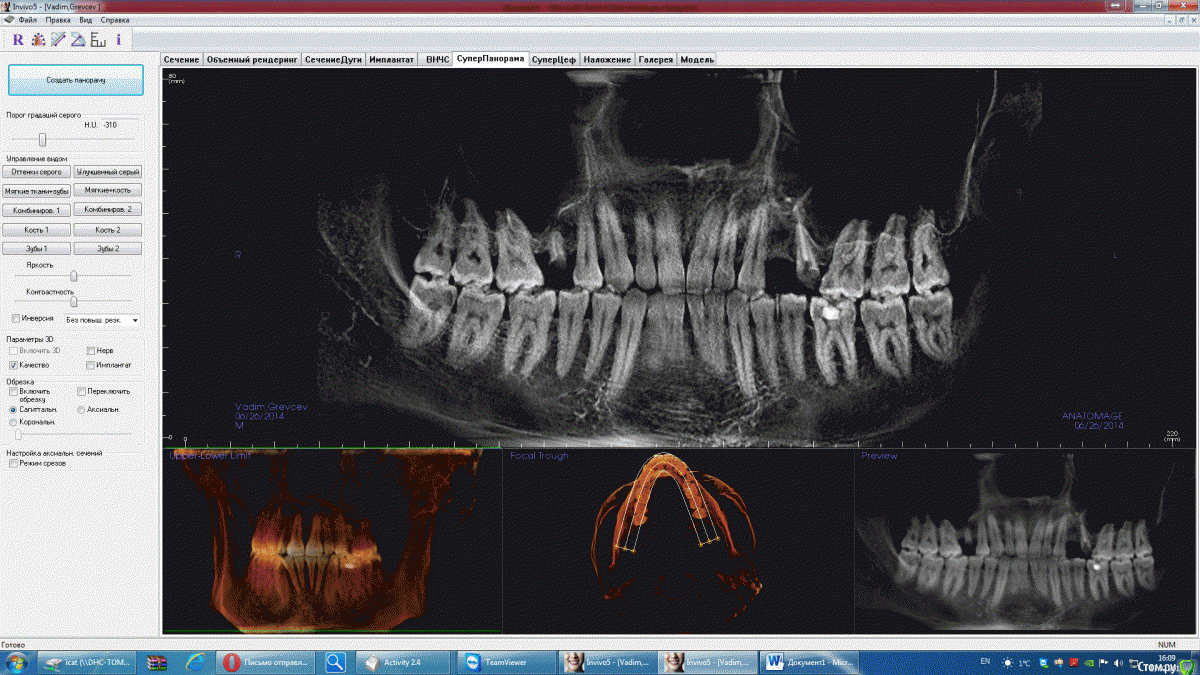

Стас756 Опубликовано 19 февраля, 2015 Поделиться Опубликовано 19 февраля, 2015 (изменено) Добрый деньудалось получить много снимковсвоего длительнгоо леченияВкратце Удаление 25 с одномоментной аугментацией и имплантацией., 24 –имплантация. 25 – периимплантит /извлечение импланта. Субантральная аугментация с использованием синтетического костного графта.После первого вмешательства появились жалобы на заложенность носа, неприятный запах, периодически возникающие боли в области левой половины головы.Общая а/б, противовоспалительная и гипосенсибилизирующая терапия не привела к улучшению.По истечении нескольких месяцев после извлечения импланта 25 зуба, появились значительные рентгенологические улучшения, хотя клинически изменений пациент не наблюдал.Далее была проведена аугментация в области 25 зуба, общая терапия.Спустя 1,5 месяца после аугментации – рентгенологические признаки левостороннего пансинусита.Жалобы – без изменений. В общем ставили два имплантаодни потом удалилисдеали синусна последней снимке налюдаетcя гайморитчто делать и с чем это может быть связано? Снимков многонадеюсь можете сказать мнение Интересует хорошо ли были поствланеы импланты вообще в самом началеи что делать сейчас?) Завтра врач должен вскрывать область 25ого зуба, но вроде сам не уверен удалять ли графт (стоит уже около 2х месяцев) у меня чувствуется странное онемение с левой стороны, появилось дня 4 назад, что это может быть? Файлы лежат по ссылкам, много весили, пришлось кинуть на файлообменник http://rghost.ru/87RM6BqXHhttp://rghost.ru/7Z4nfBXK7 Изменено 19 февраля, 2015 пользователем Стас756 Ссылка на комментарий

Стас756 Опубликовано 19 февраля, 2015 Автор Поделиться Опубликовано 19 февраля, 2015 Вот что получаетсяэто до и после имлпанатциине знаю на сколько нформативно Ссылка на комментарий

Стас756 Опубликовано 19 февраля, 2015 Автор Поделиться Опубликовано 19 февраля, 2015 (изменено) Вроде всепоследние фото это с удаленным имплантом и после синуслифтингабыл бы благодарен за мненияесли можно что-то сказать по снимкамибо врач похоже сам не понимает почему гайморит уже второй разто имплант извлектеперь похоже надо костный материал извлекать Изменено 19 февраля, 2015 пользователем Стас756 Ссылка на комментарий

Bier Опубликовано 19 февраля, 2015 Поделиться Опубликовано 19 февраля, 2015 КТ делать можно.Ваши снимки не информативны. Надо оценить состояние соустья. Оценить жизнеспособность костного материала по рентгену невозможно. Возможно требуется ревизия. Ссылка на комментарий